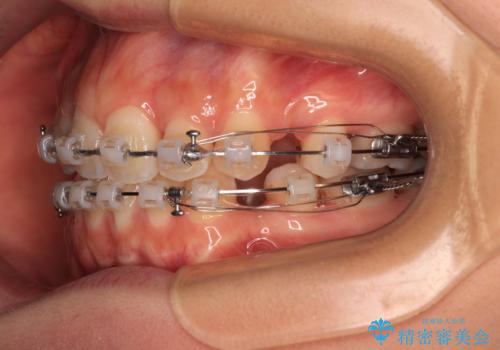

- 矯正装置

- クリアブラケット

- 前歯のデコボコと口元の突出感を気にして来院された患者様です。

口元の突出感が認められ、更には左右で異なる咬合状態であったため、下顎右側は第二小臼歯を、左側は第一小臼歯を抜去することでバランスを取るような治療計画としました。

下顎の抜歯位置を左右で変えることで、最終的に上下正中をほぼ一致させることができました。